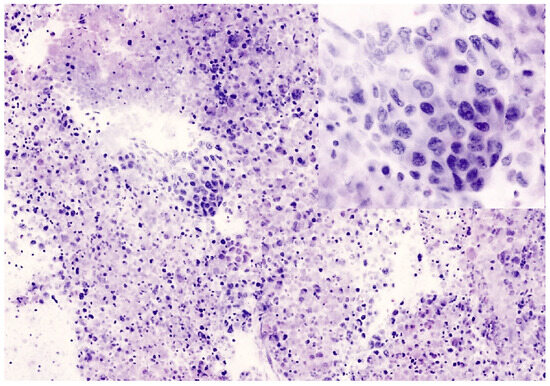

Figure 4. Small cell carcinoma of the lung hilum. (a) In FCM image, malignant cells of small size are arranged in loose sheets and show round nuclei with fine chromatin, no evidence of nucleoli, and scant cytoplasm. Nuclear molding is recognizable (inset). (b) Permanent paraffin section from the same case. Malignant small cells are loosely cohesive and associated with nuclear crashing and necrosis. Immunohistochemistry for neuroendocrine markers resulted positive.